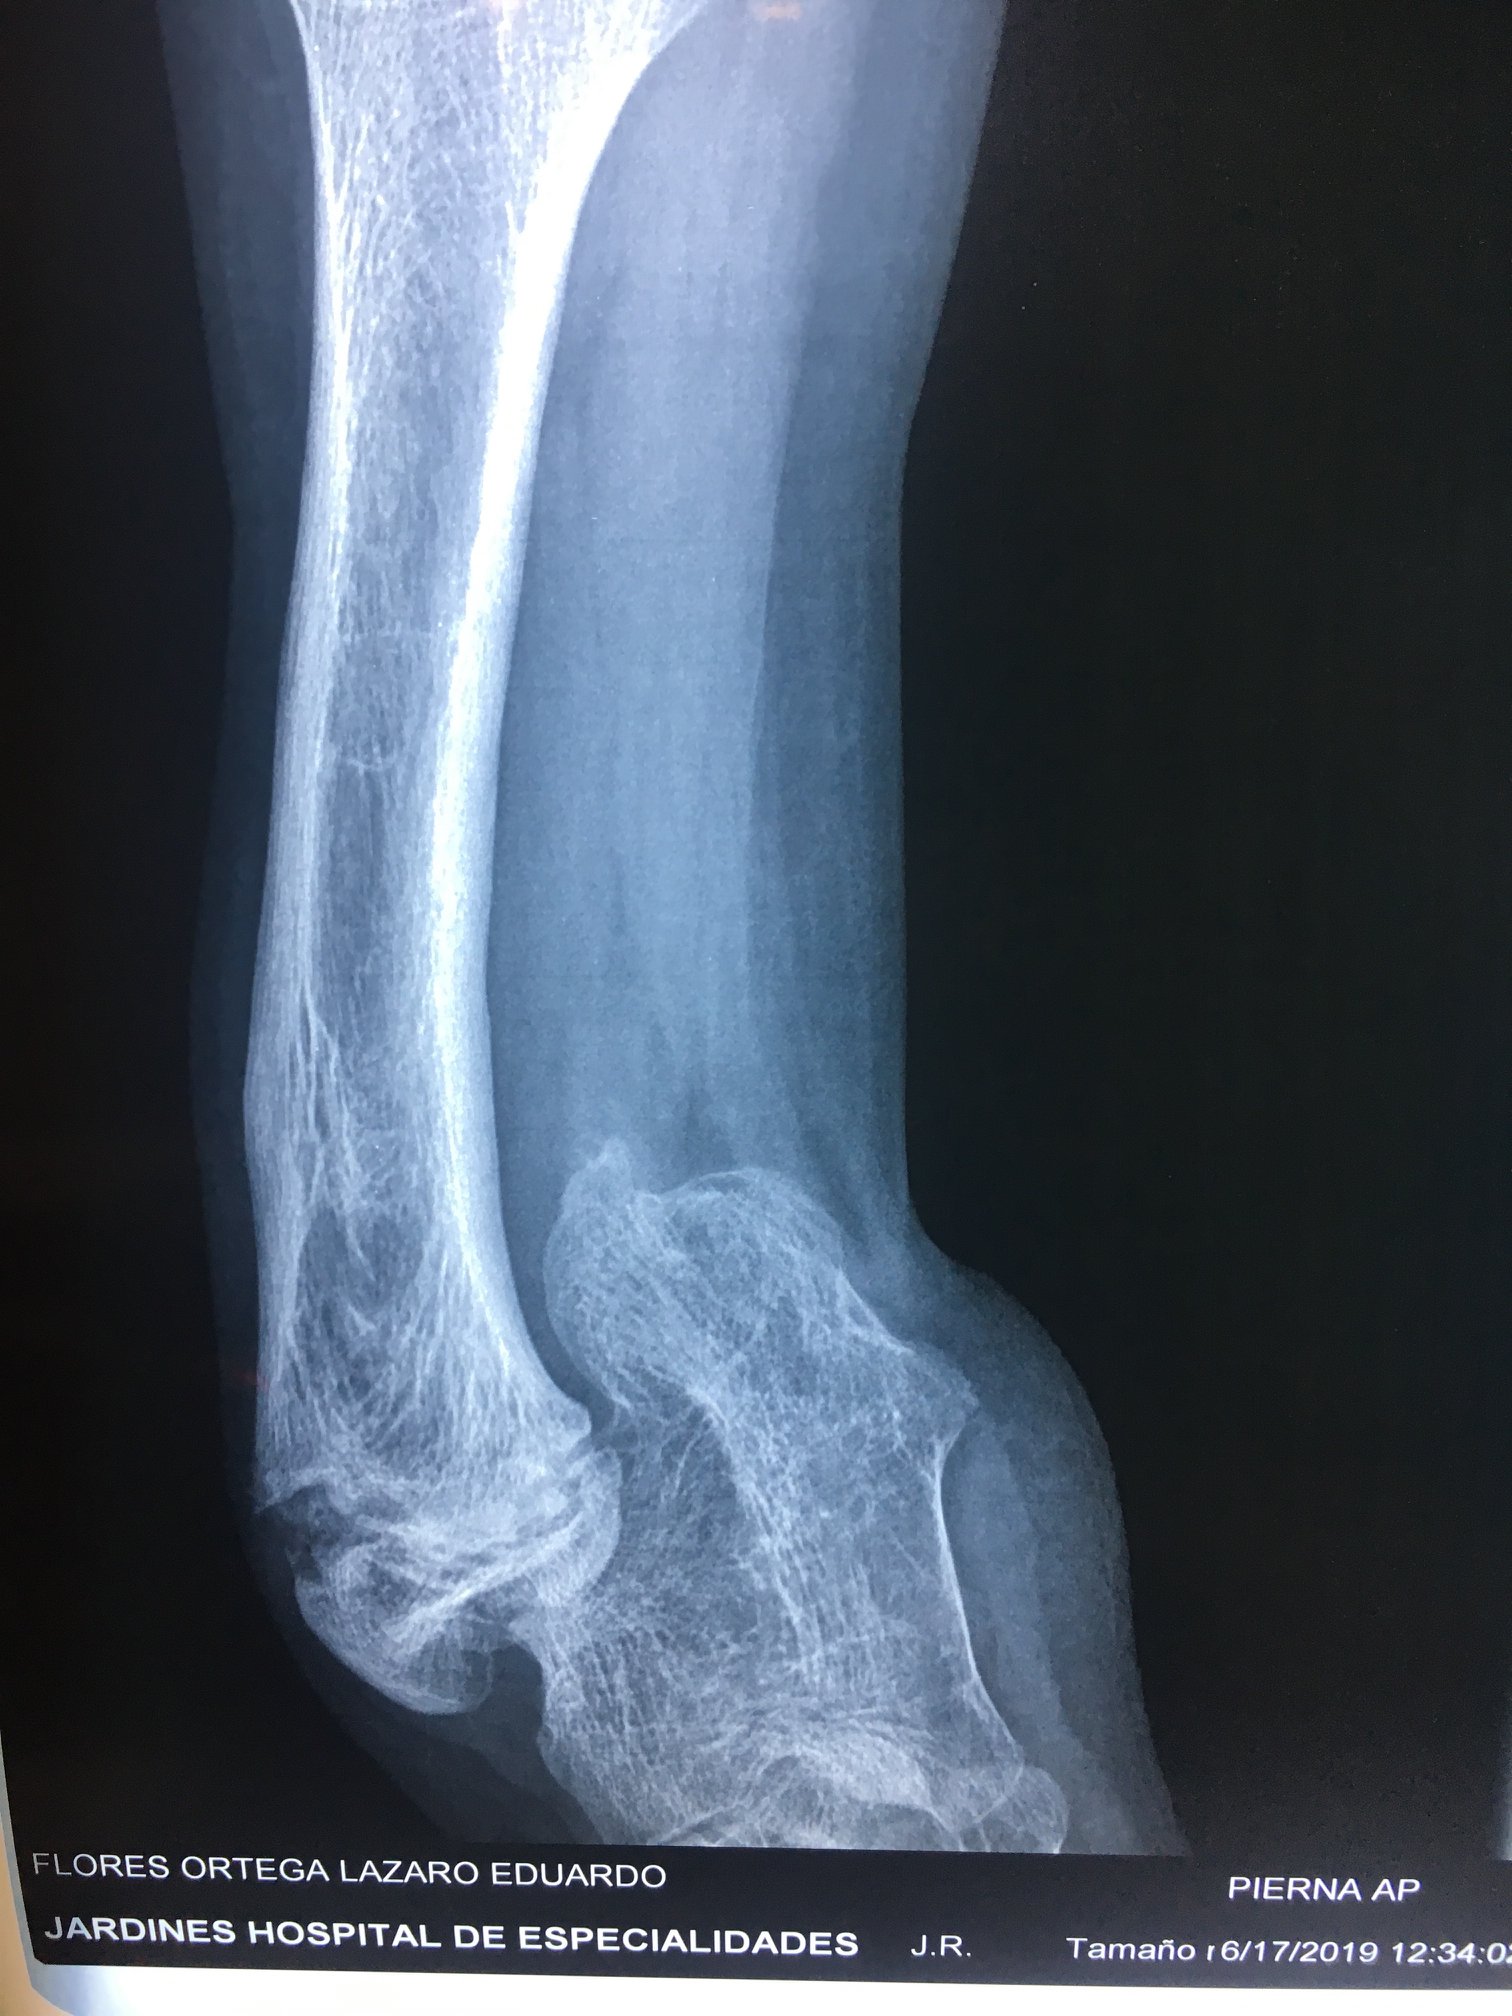

Ausencia congenita del peroné

A los papás de Lazarito les dijeron en Estados Unidos que la única alternativa para su hijo era una amputación; buscando segundas opiniones, llegaron conmigo. Lazarito, de 13 años, tiene #hemimelia #perónea, una ausencia congénita del peroné que causa malformaciones y acortamientos. Para evitar la amputación, se le realizó una reconstrucción del tobillo y alineamos su pierna de forma funcional. Ahora, mi pacientito ya camina con apoyo al 100%, realiza sus actividades diarias y dice que empezará a jugar fútbol. Agradezco a sus papás por la confianza y a sus familiares en Guadalajara por recomendarlo conmigo.